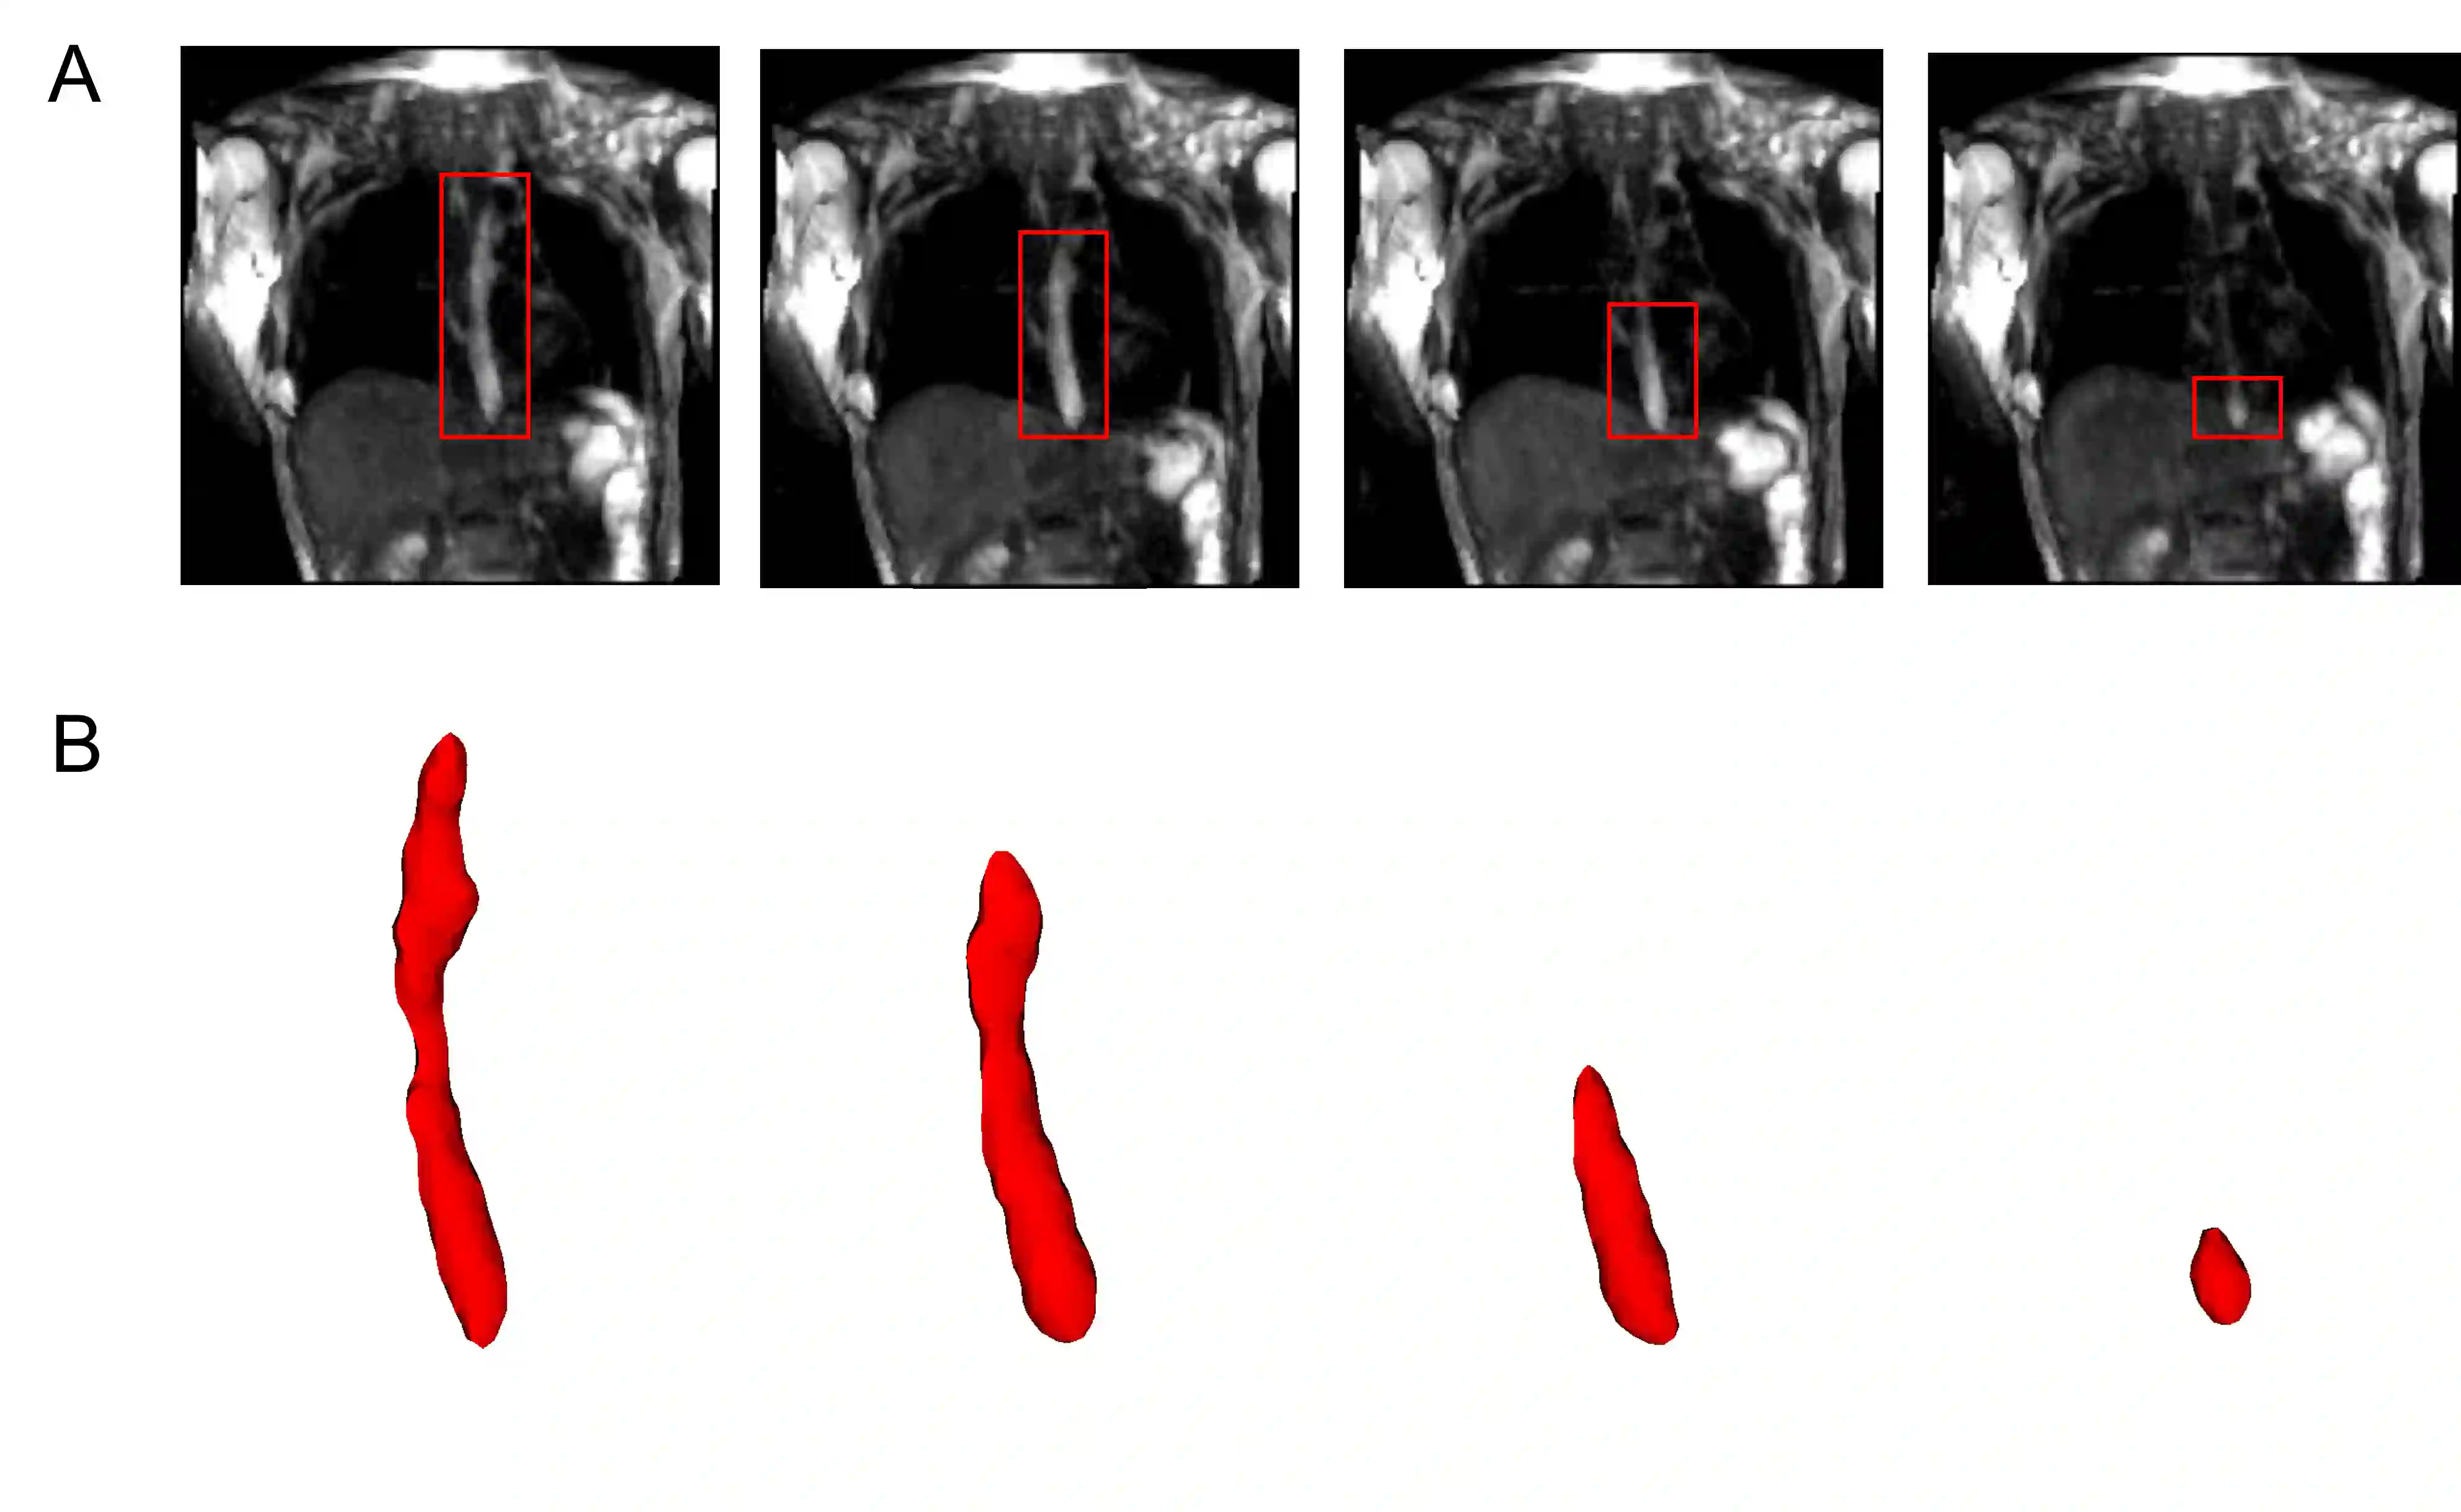

Dynamic magnetic resonance imaging (MRI) is a popular medical imaging technique to generate image sequences of the flow of a contrast material inside tissues and organs. However, its application to imaging bolus movement through the esophagus has only been demonstrated in few feasibility studies and is relatively unexplored. In this work, we present a computational framework called mechanics-informed MRI (MRI-MECH) that enhances that capability thereby increasing the applicability of dynamic MRI for diagnosing esophageal disorders. Pineapple juice was used as the swallowed contrast material for the dynamic MRI and the MRI image sequence was used as input to the MRI-MECH. The MRI-MECH modeled the esophagus as a flexible one-dimensional tube and the elastic tube walls followed a linear tube law. Flow through the esophagus was then governed by one-dimensional mass and momentum conservation equations. These equations were solved using a physics-informed neural network (PINN). The PINN minimized the difference between the measurements from the MRI and model predictions ensuring that the physics of the fluid flow problem was always followed. MRI-MECH calculated the fluid velocity and pressure during esophageal transit and estimated the mechanical health of the esophagus by calculating wall stiffness and active relaxation. Additionally, MRI-MECH predicted missing information about the lower esophageal sphincter during the emptying process, demonstrating its applicability to scenarios with missing data or poor image resolution. In addition to potentially improving clinical decisions based on quantitative estimates of the mechanical health of the esophagus, MRI-MECH can also be enhanced for application to other medical imaging modalities to enhance their functionality as well.